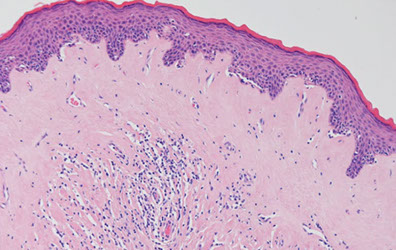

Balanitis Xerotica Obliterans

- aka lichen sclerosus et atrophicus

A chronic progressive sclerosing process of inner foreskin that frequently results in urethral stenosis usually in middle-aged men that could be 2/2 autoimmune dz

Micro: identical to lichen slerosus et atrophicus (red white and blue babyyy!) of vulva, a chronic and atrophic mucocutaneous dz

- thin or thick epidermis with orthokeratotic hyperkeratosis

- vacuolar degen of basal layer, diffuse fibrosis and deep lymph infiltrate